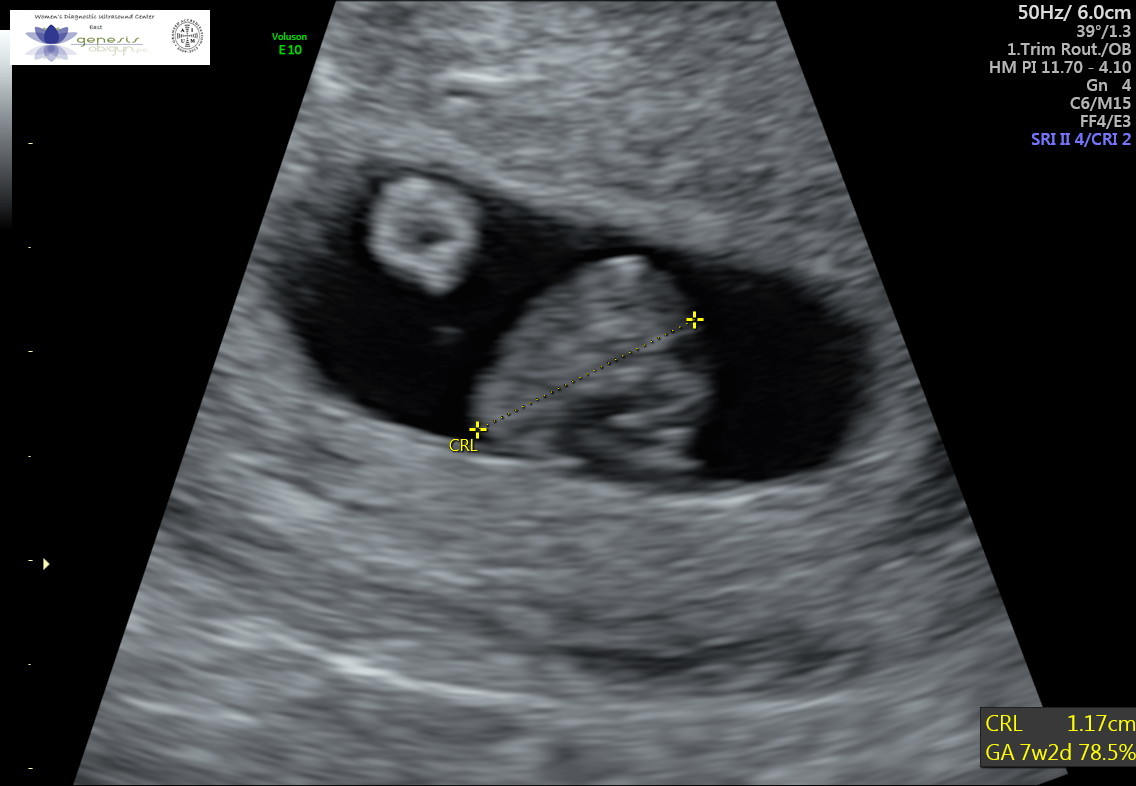

It is measurable sonographically from around 6 weeks and the normal range varies during gestation, increasing to around 170 bpm at 10 weeks and decreasing from then to around 130 bpm at term. Mine was 85 at 6 weeks 3 days, everything else looked perfect. Many factors can cause a child’s vital signs to deviate from the norm. How long.

We started with a precise definition of “normality” and performed a retrospective computerized analysis of electronically recorded fhr tracings. It is measurable sonographically from around 6 weeks and the normal range varies during gestation, increasing to around 170 bpm at 10 weeks and decreasing from then to around 130 bpm at term. Current international guidelines recommend for the normal fetal.

:) both of them were girls. Your baby's heart starts beating when you enter 6 th week of your pregnancy. It is measurable sonographically from around 6 weeks and the normal range varies during gestation, increasing to around 170 bpm at 10 weeks and decreasing from then to around 130 bpm at term. The ultrasound lady said not to worry,.